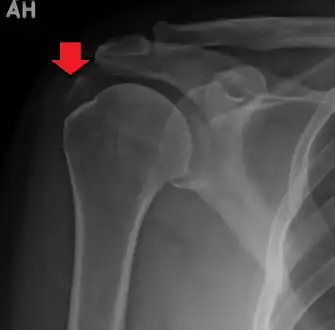

An x-ray showing calcific deposits in the area of the tendons of the rotator cuff muscles